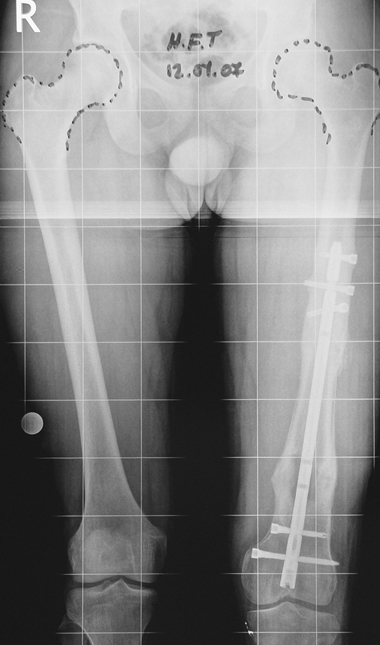

Bu Bacak Kısalık tipi bir kırığın kısalmış pozisyonda kaynaması ile oluşur. Bir çok vaka yetişkinlerde görülür ve sadece bir uzatma ile tedavi edilebilir. Ek deformiteler de aynı anda düzeltilebilir. Bu hastaların çoğu çivi üzerinden uzatma veya tam implante edilen çivi ile tedavi edilebilirler.